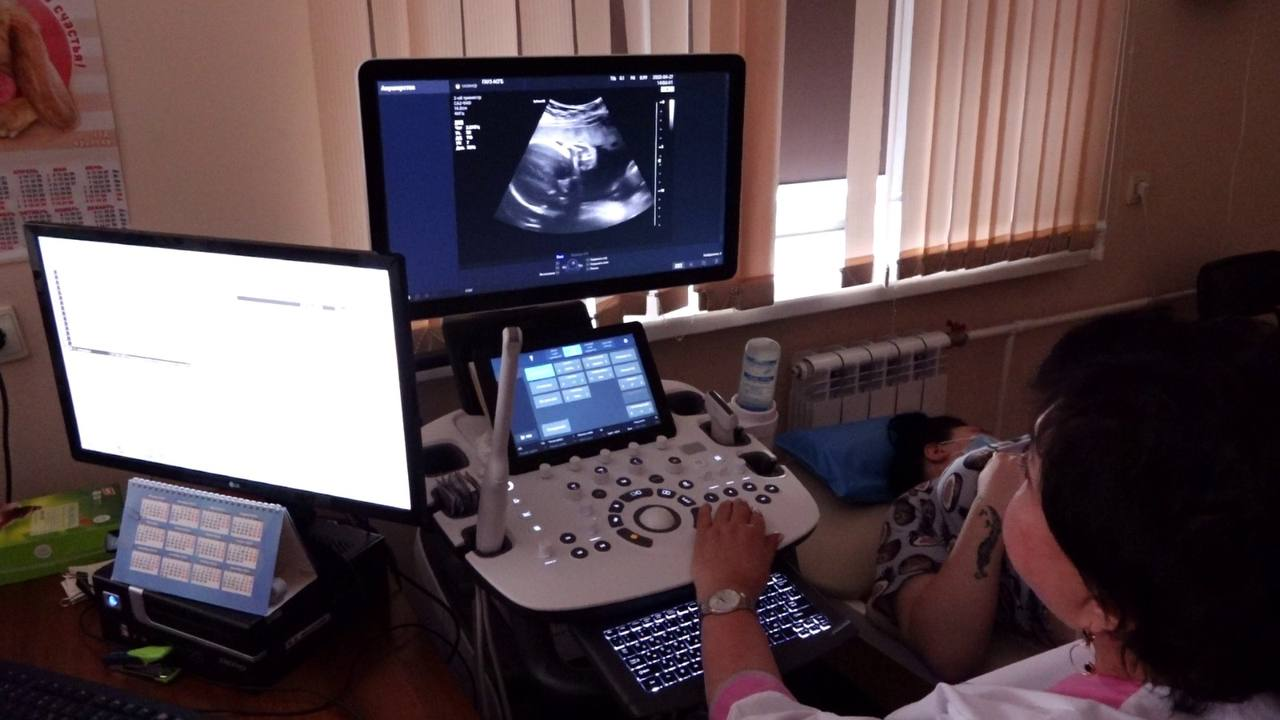

В Мариинскую городскую больницу им. В.М. Богониса закуплена стабилоплатформа с биологической обратной связью и передвижной ультразвуковой аппарат. Также в Анжеро-Судженскую городскую больницу им. А. А. Гороховского поступил передвижной ультразвуковой аппарат для исследования сердца и сосудов «РуСкан 65».